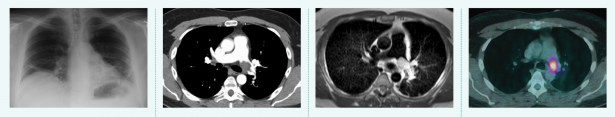

Tools of the trade, from left to right. 1. Radiography Passes X-rays through a patient to produce an image on film or digital detector. 2. Computed Tomography (CT) Uses X-rays and computer processing to generate cross-sectional “slices” and 3D images. 3. Magnetic Resonance Imaging (MRI) Uses strong magnetic fields to excite hydrogen atoms and detects the radio frequency signals they emit. 4. Positron Emission Tomography (PET) Detects gamma rays produced by a radioactive tracer in a biologically active molecule. The most commonly used molecule, fluorodeoxyglucose (FDG), marks tissues that are metabolically active, such as tumor metastases.